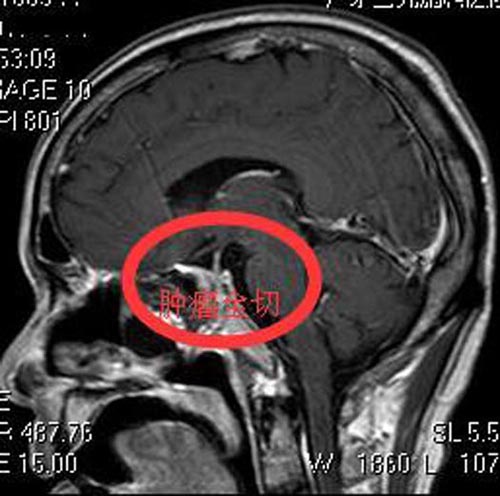

广东三九脑科医院垂体瘤诊疗中心查体发现:神志清醒,双侧瞳孔等圆等大,右眼视力0.6,左眼视力1.0,头颅MR检查显示:鞍区占位性病变,3.4cm×3.9cm×2.9cm,考虑垂体大腺瘤。

李先生积极要求手术治疗。由鲁明主任主刀,全麻内镜下经鼻蝶垂体大腺瘤切除+颅底重建,术中见肿瘤呈灰白色,质软,将肿瘤全切除,手术经过顺利。术后李先生无脑脊液漏、尿崩、离子紊乱等并发症,视力明显较前好转,康复出院。术后病理结果提示:垂体腺瘤,WHO I级。

▲手术前